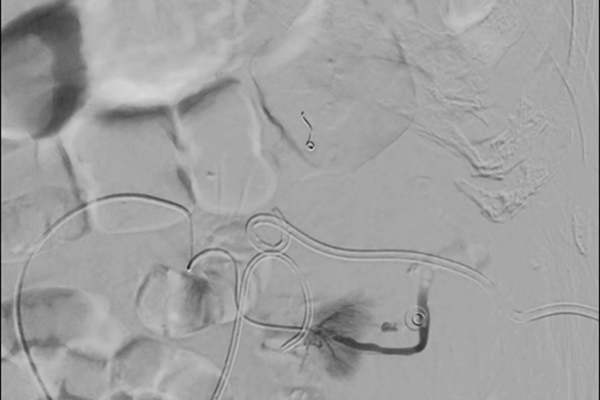

The role of embolisation in urology

Benign upper tract abnormalities